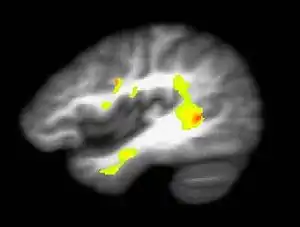

Ação da Cannabis sativa e Cannabis indica no sistema nervoso central

O delta-9 THC, após chegar ao encéfalo é absorvido por receptores específicos, as anandamidas. São encontradas altas densidades de receptores de THC no córtex cerebral, hipocampo, cerebelo e gânglios basais, o que explica os respectivos efeitos físicos e mentais associados ao consumo da droga:

Os receptores de THC localizam-se especificamente nos neurônios do sistema de opioides endógenos (Sistema relacionado a secreção de substâncias opioides pelo próprio organismo),a partir da ligação do THC com seus receptores localizados nesse sistema há uma excitação dos neurônios componentes do mesmo, que enviam sinais aos neurônios dopaminérgicos do sistema límbico (responsável principalmente pela regulação dos processos emocionais), suscitando a liberação de mais dopamina (neurotransmissor relacionado a sensação de prazer) dando sensação de prazer e euforia. A ação no sistema límbico, que além da regulação dos processos emocionais está relacionado a memória de curto prazo, também explica portanto, a "falha" de retenção desse tipo de memória. É importante ressaltar,contudo, que apesar da memória de curto prazo não estar intimamente relacionada com a aprendizagem, a memória de longo prazo, relacionada com esse fato, pode se formar a partir da memória de curto prazo , que tem a possibilidade de ser armazenada temporariamente e depois transferida para áreas relacionadas com a memória de longo prazo.